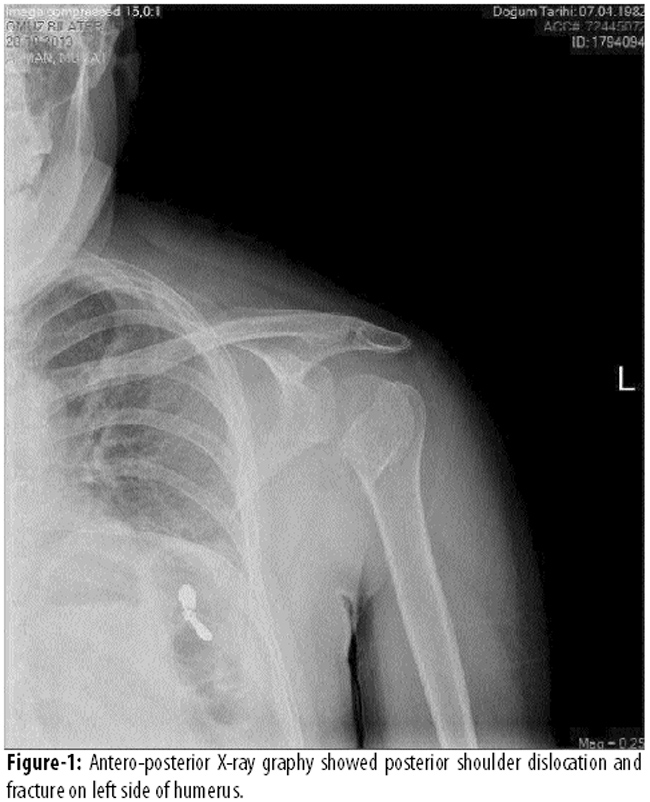

A 32 year-old-male patient was admitted to emergency department with difficulty to move both of the arms. In the anamnesis, we learned from the family members, 3 hours before the admission the patient had an attack of loss of consciousness, deviation of the eyes and urinary incontinence, which lasted for 3 minutes. The patient had no history of convulsion or another chronic disease or medication. On admission the patient was cooperative and oriented. He complained of shoulder pain especially on movements. On physical examinations the blood pressure was 140/85 mmHg, pulse rate; 102 beats/minute and regular, and temperature was 36.7ºC. Muscle power of bilateral proximal upper extremities were 1/5 and 5/5 for distal part of the extremities. Cerebellar tests could not be performed because of problem with shoulder movements. There was no abnormal value in blood count and biochemical values except elevated creatine-kinase (650 U/L, normal; 39-308 U/L). In order to exclude an intracranial pathology, a brain CT scan was performed which was normal. To investigate the cause of shoulder pain, an antero-posterior X-Ray was performed which showed bilateral posterior shoulder dislocation and fracture on the left side (Figure-1).